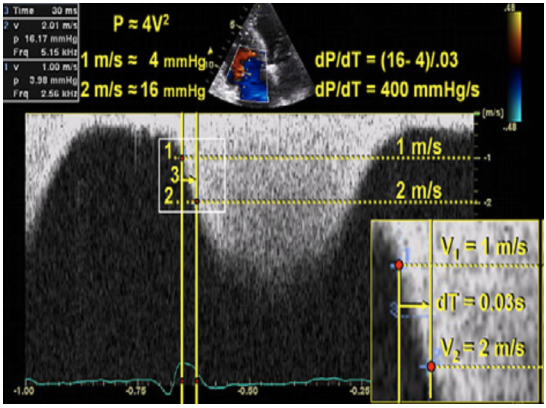

(5)右心室dp/dt(等容收缩期右心室压力变化速率)图18:在三尖瓣反流的连续多普勒(CW)信号中,将卡尺定在1 m/s和2 m/s之间来确定三尖瓣反流的压力,再根据简化的伯努利方程来确定dp/dt=12 mmHg/[TR时间1(m/s)-TR时间2(m/s)]。正常参考值为237.5~272.5 mmHg/s,随着右心功能的降低,该值也将明显增加。一般大于400 mmHg/s认为有重要的临床意义。

图片

图18. 右心室dp/dt测量